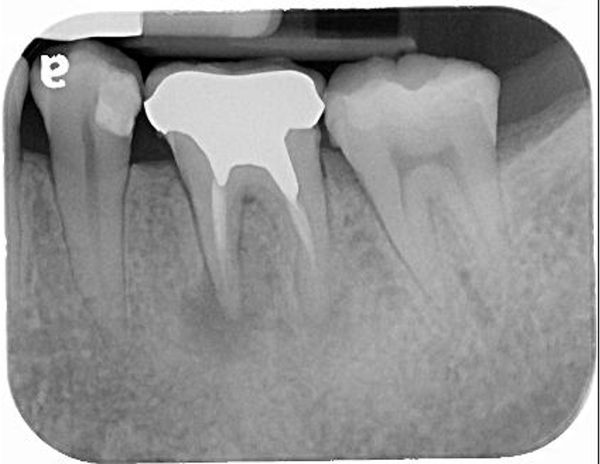

根尖病變

電腦斷層確認根尖病變